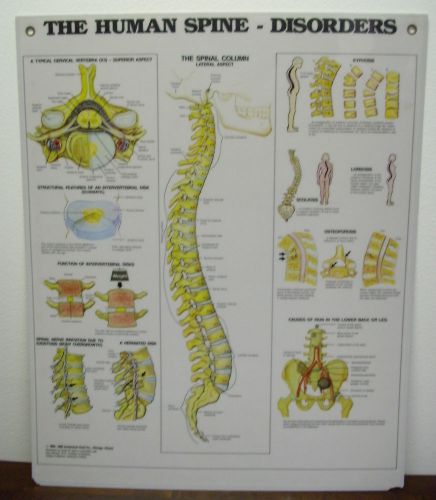

Laminated Anatomical Wall Chart " The Human Spine Disorders"